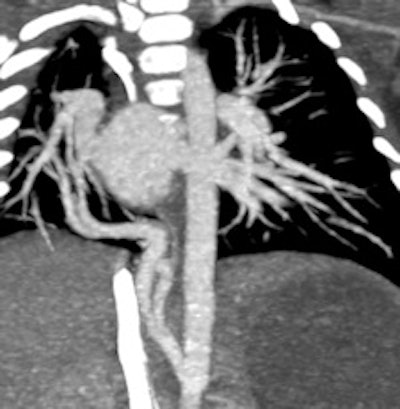

Prospective ECG-gated study on an unsedated free-breathing 2-month-old girl with an average heart rate of 122 beats per minute (bpm). The right pulmonary artery is hypoplastic (top left). An aortopulmonary collateral arising from the celiac axis supplies the right lung, as shown in the volume-rendered image (top right) and the maximum intensity projection image (bottom). All figures courtesy of Carolyn Young.